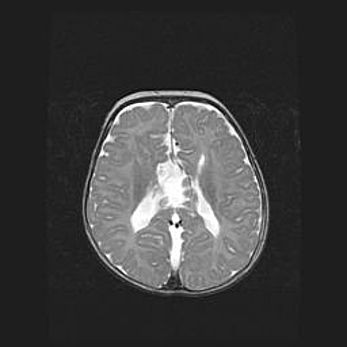

Множественные кисты обоих полушарий головного мозга, наибольшая из них в правой затылочной области. Ассиметричная атрофическая гидроцефалия.

Возраст: 7 месяцев

Вес: 5660 г

Пол: мужской

Окружность головы: 41,5 см

Срок гестации: 28-29 недель

Кисты головного мозга развиваются в результате многоочаговых некрозов вещества мозга и возникают вследствие перенесенной перинатальной инфекции, менингитов, энцефалитов, асфиксии, родовой травмы, расстройств мозгового кровообращения различного генеза. Образованию кист в веществе головного мозга плодов и новорожденных способствуют такие факторы, как высокое содержание в нем воды, недостаточная (или отсутствие) миелинизация и слабая астроглиальная реакция на повреждение.

Кисты могут сочетаться с гидроцефалией и другими поражениями головного мозга.